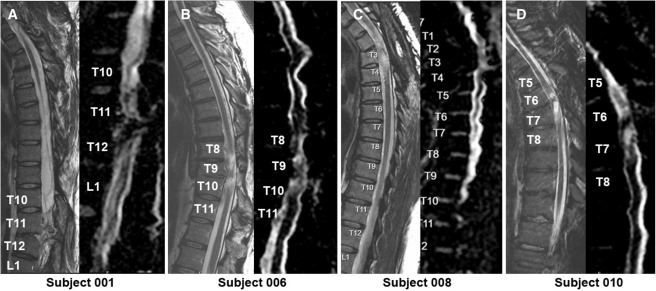

本次发布的I期临床研究旨在评估神经干细胞移植治疗慢性胸椎脊髓损伤的安全性和初步疗效。研究选取了四名完全性ASIA-A级胸部SCI患者作为受试者,这些患者的损伤时间均超过一年,且在接受任何其他形式的有效治疗后仍未见明显好转。

每位受试者接受了每个注射点含有2×105个神经干细胞,通过定制的立体定向设备,双侧注入损伤部位周围的剩余组织及下方约一个节段的内侧白质区,整个过程由术中荧光透视成像指导完成。

1.神经系统反应概览:按ISNCSCI随访,2名受试者(001、010)在移植后出现了明显的神经学改善:001在移植后2年曾上升两个节段,5年回落至上升1个节段;010则在整个5年随访期间保持了稳定的神经功能提升。

4.影像学评估:术后MRI显示所有患者存在不同程度的局灶性脊髓软化,但未见新的并发影像学征象(如水肿、增强或积液);DTI提示脊髓束外观稳定,未见广泛重塑或纤维束改善。